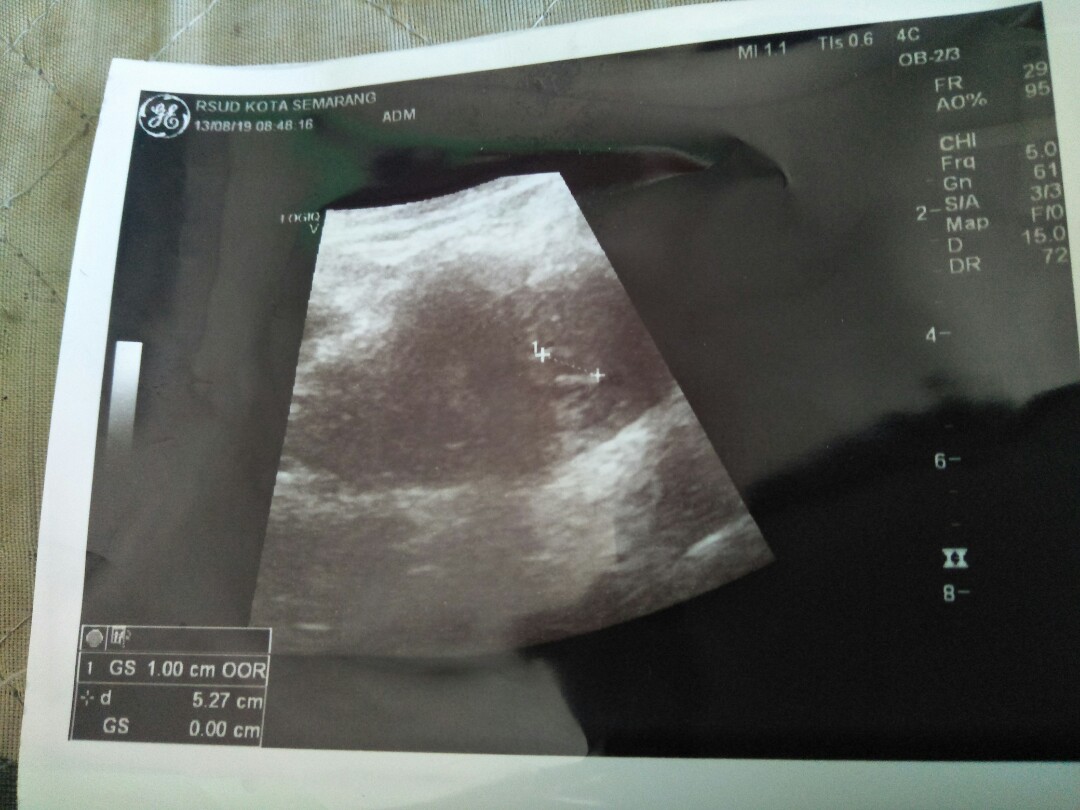

ini usg ku usia 5week 4day masih 1cm bun, susah diusg disarankan usg diusia 8week